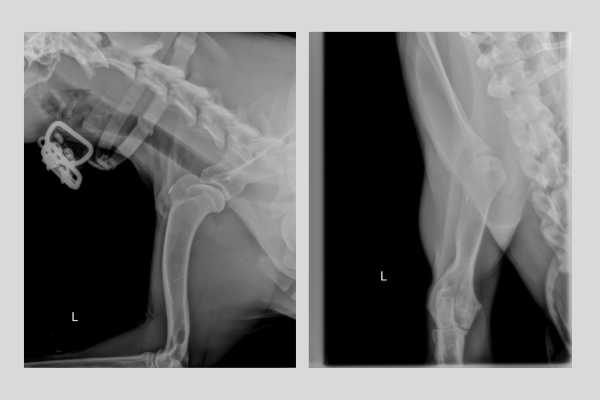

Se realizan radiografías ortogonales del húmero dado que nos pueden orientar en nuestros diagnósticos diferenciales.

En ellas se detecta un aumento de opacidad del canal medular en el tercio distal del húmero derecho.

Diagnóstico

Con las imágenes radiológicas el diagnóstico de panosteitis se confirma.

- Generalmente, las radiografías suelen ser diagnósticas según el estadio de la enfermedad en el momento de la evaluación, pudiendo detectarse asimismo mediante TC o RM.